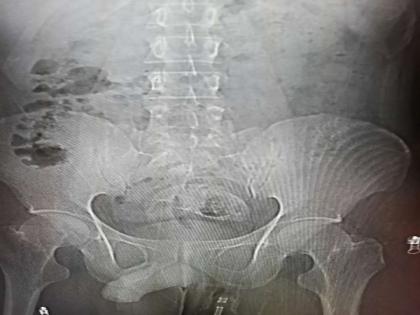

या व्यक्तीचं वय 30 आहे. झाओकिंग पीपल्स हॉस्पिटलमध्ये त्याचं ऑपरेशन करण्यात आलं. यात 16 इंच लांब एक पूर्ण मासा बाहेर काढण्यात आला. व्यक्तीच्या उत्तराने डॉक्टर हैराण आहेत. ते म्हणतात की, कोणतीही व्यक्ती कपड्यांविना माशावर का बसेल? जर तो बसला तरी मासा त्याच्या शरीरात शिरत आहे हे त्याला समजलं कसं नाही. ही घटना चीनमधील सोशल मीडियावर व्हायरल झाली आहे.

डॉक्टरांनी सर्जिकल ऑपरेशन करून मासा काढला. त्यांनी सांगितले की, हा मासा त्याच्या गदद्वारात अनेक दिवसांपासून होता. जर आणखी थोडा उशीर झाला असता तर गंभीर समस्या झाली असती. मासा आतल्या आत सडू लागला होता. त्यामुळे रेक्टमसोबतच पोटातली इन्फेक्शन पसरलं होतं. सध्या ही व्यक्ती ठिक आहे.